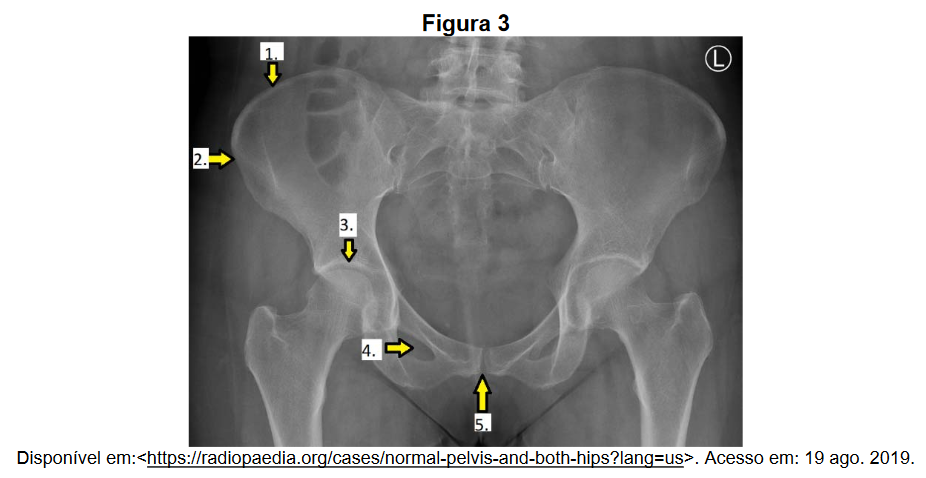

O conhecimento anatômico radiográfico é fundamental na prática dos exames radiográficos. Na figura 3, estão destacados alguns pontos anatômicos.

A alternativa que contém a correta identificação dos pontos anatômicos destacados na figura 3 é